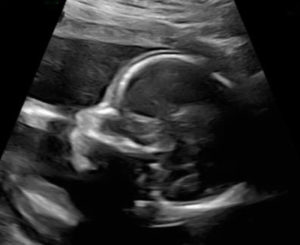

Currently almost 21 weeks along with our miracle baby girl and we are both doing wonderful.